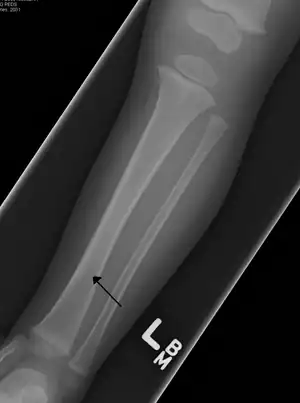

| A toddler's fracture | |

Toddler's fracture is a type of broken bone that involves the lower part of the shin bone (tibia).[1] Symptoms may include pain in the lower leg or a limp.[1] Some refuse to walk at all.[2]

The cause is often a twisting motion over a planted foot.[1] This may occur as the result tripping or other minor events.[1] It generally occurs in the distal thirds of the tibia, is undisplaced, and has a spiral pattern.[1] Diagnosis is often based on symptoms and examination, with initial X-rays appearing normal in about half of cases.[1]

The initial radiographical images may be inconspicuous (a faint oblique line) and often even completely normal.[7] After 1–2 weeks however, callus formation develops.

Accidental or innocent toddler fracture/frontal -

Accidental or innocent toddler fracture/lateral